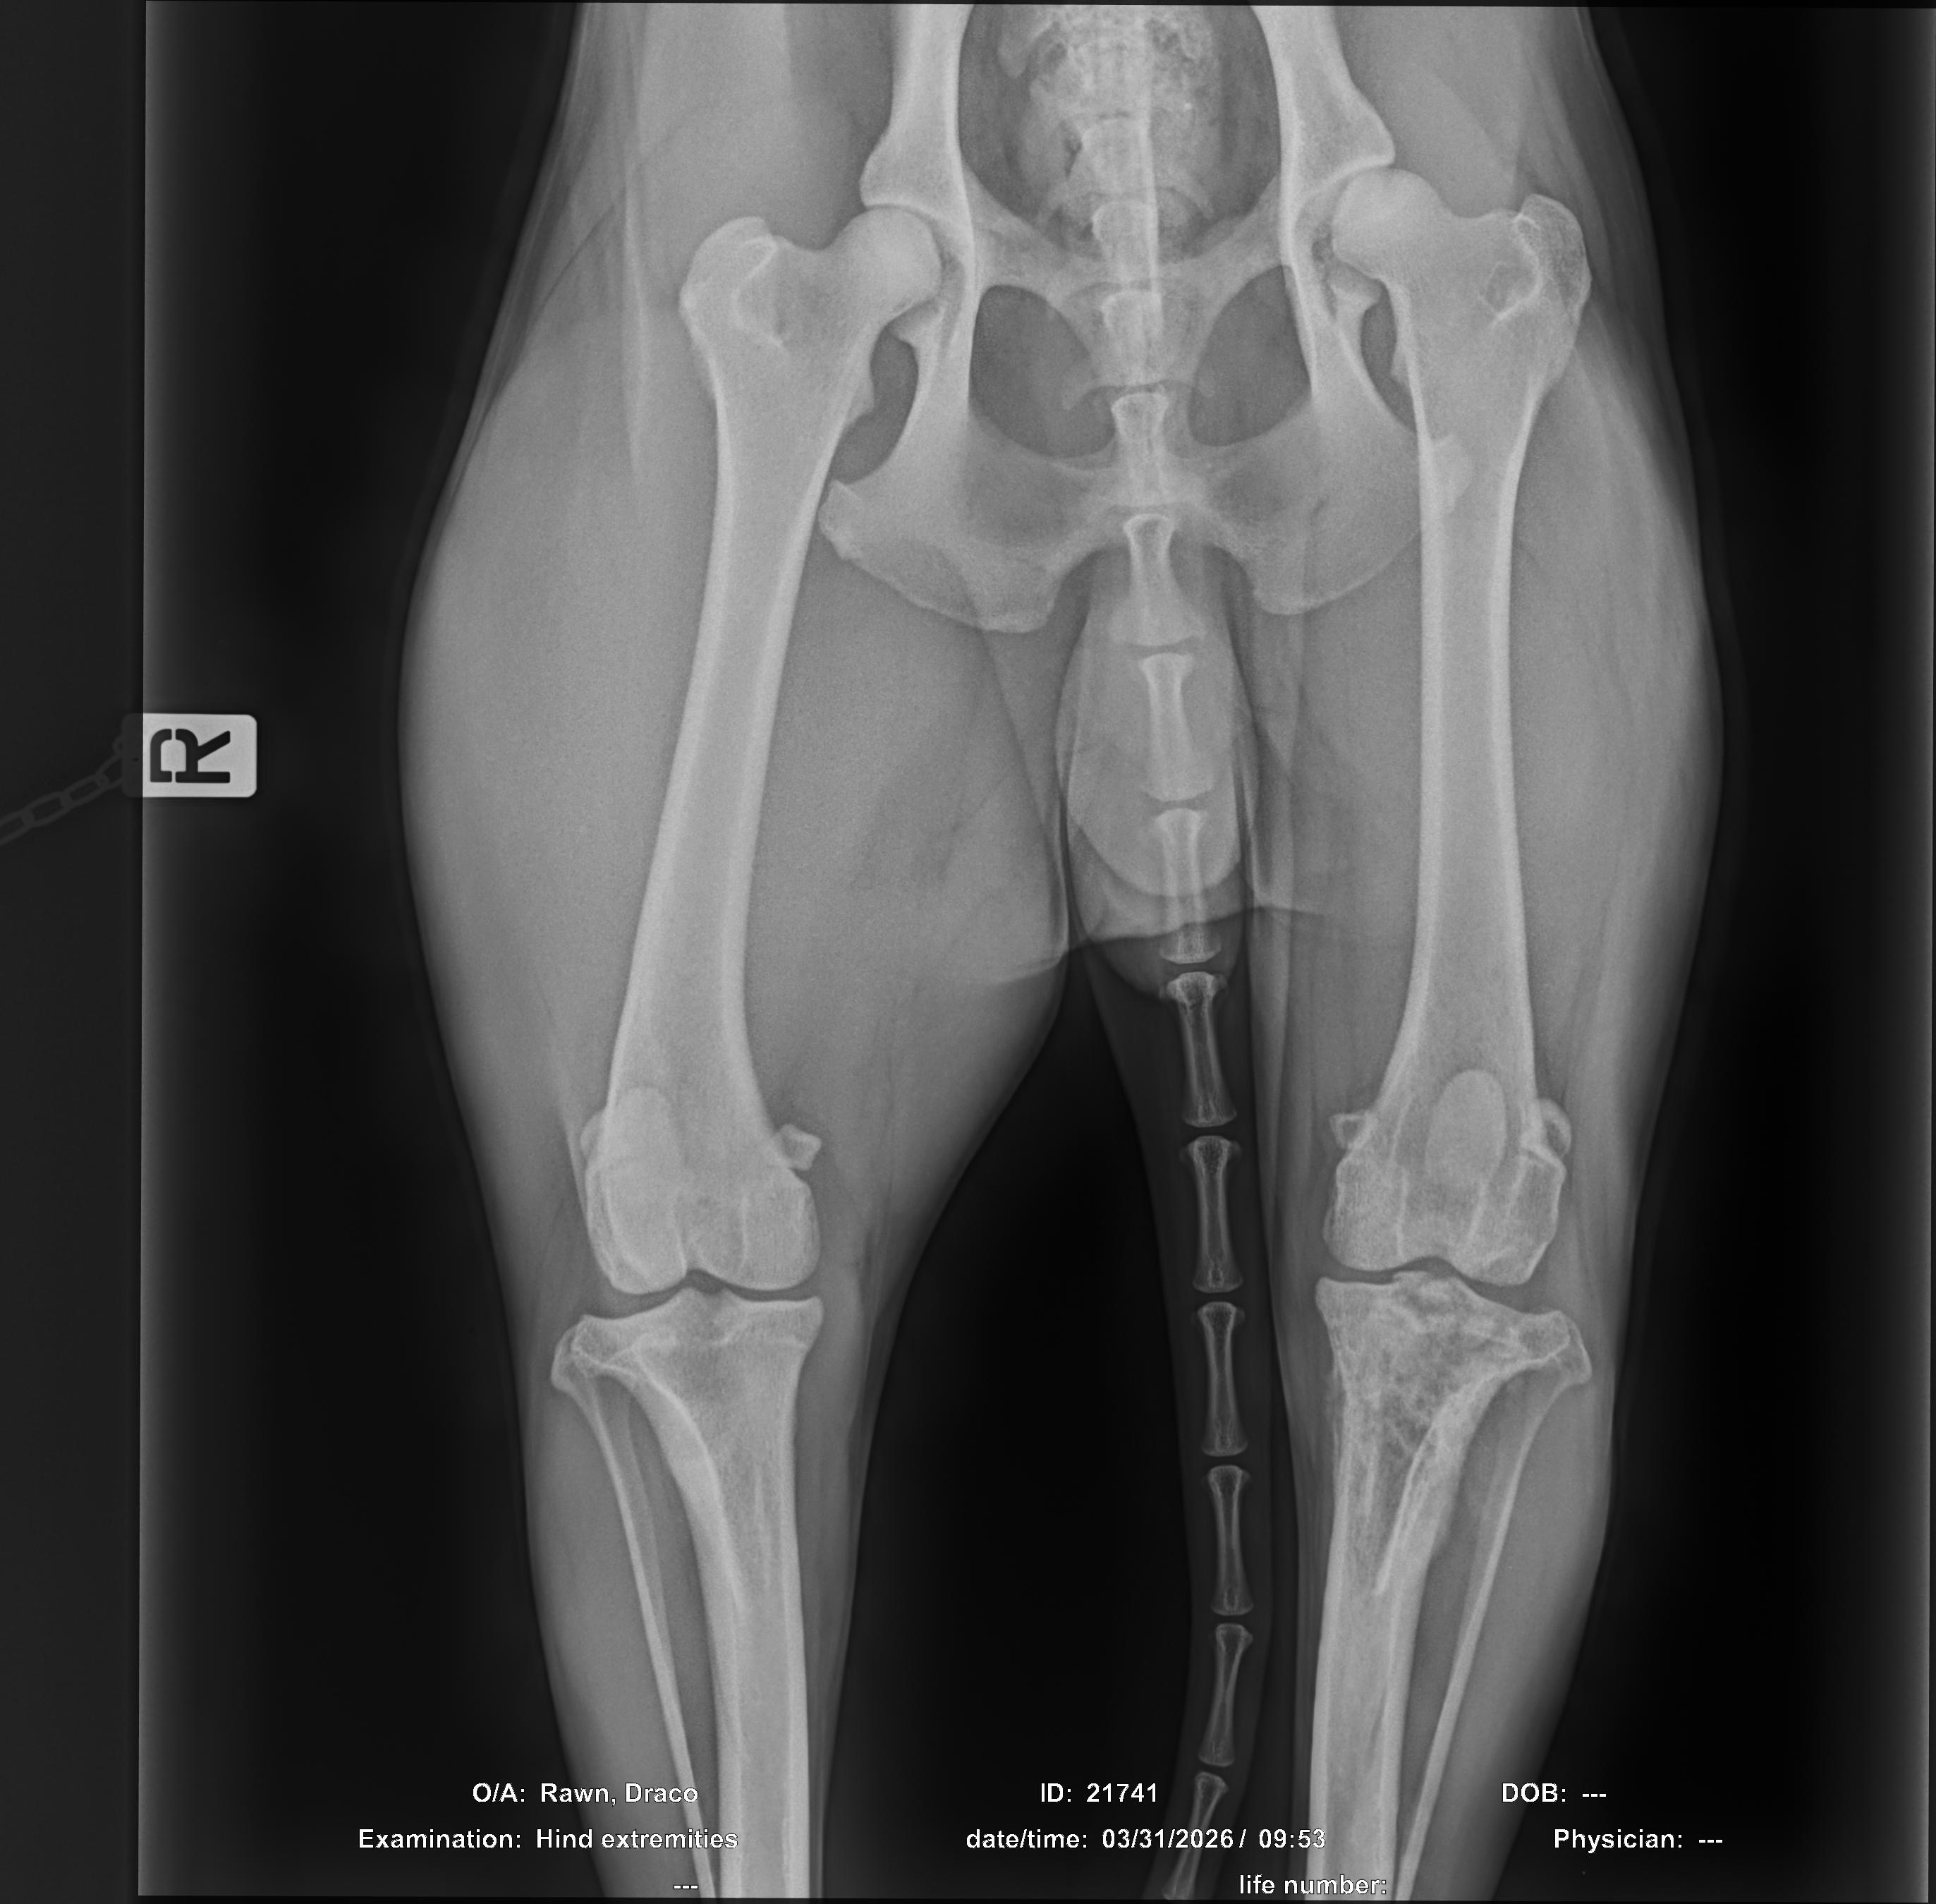

About two months ago, I started noticing something wasn’t right with his left leg. After vet visits and tests, I received the devastating news that Draco has cancer in his leg. Hearing that at such a young age has been heartbreaking.